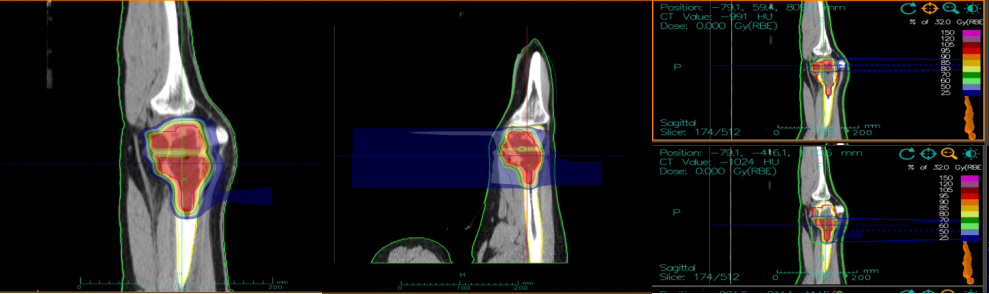

病例一:白某某,女,14岁,甘肃金昌。诊断:右股骨骨肉瘤 cT2N0M0 ⅡB,KPS:70。该患儿骨肉瘤未采用手术,直接行重(碳)离子治疗,同期完成6个周期化疗,无其他治疗。重(碳)离子治疗后66个月,已达痊愈。

治疗前重离子计划,见股骨下端130mm大小骨肉瘤

目前重(碳)离子治疗后66个月,现已痊愈。